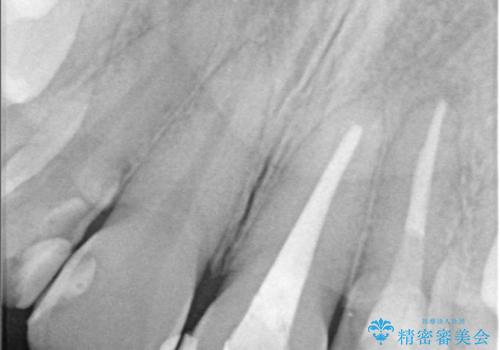

診査・診断:

左上1番および2番は失活歯であり、両歯ともに失活に伴う変色を認めました。左上2番に関しては根尖部に透過像を認め、根尖性歯周炎と診断しました。これが前歯部の痛みの原因と考えられました。